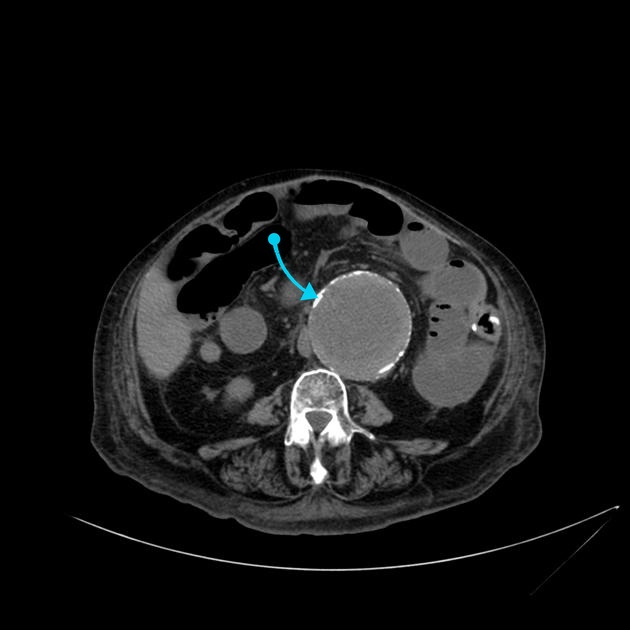

Puzzle 44 annotated

What's the Diagnosis?